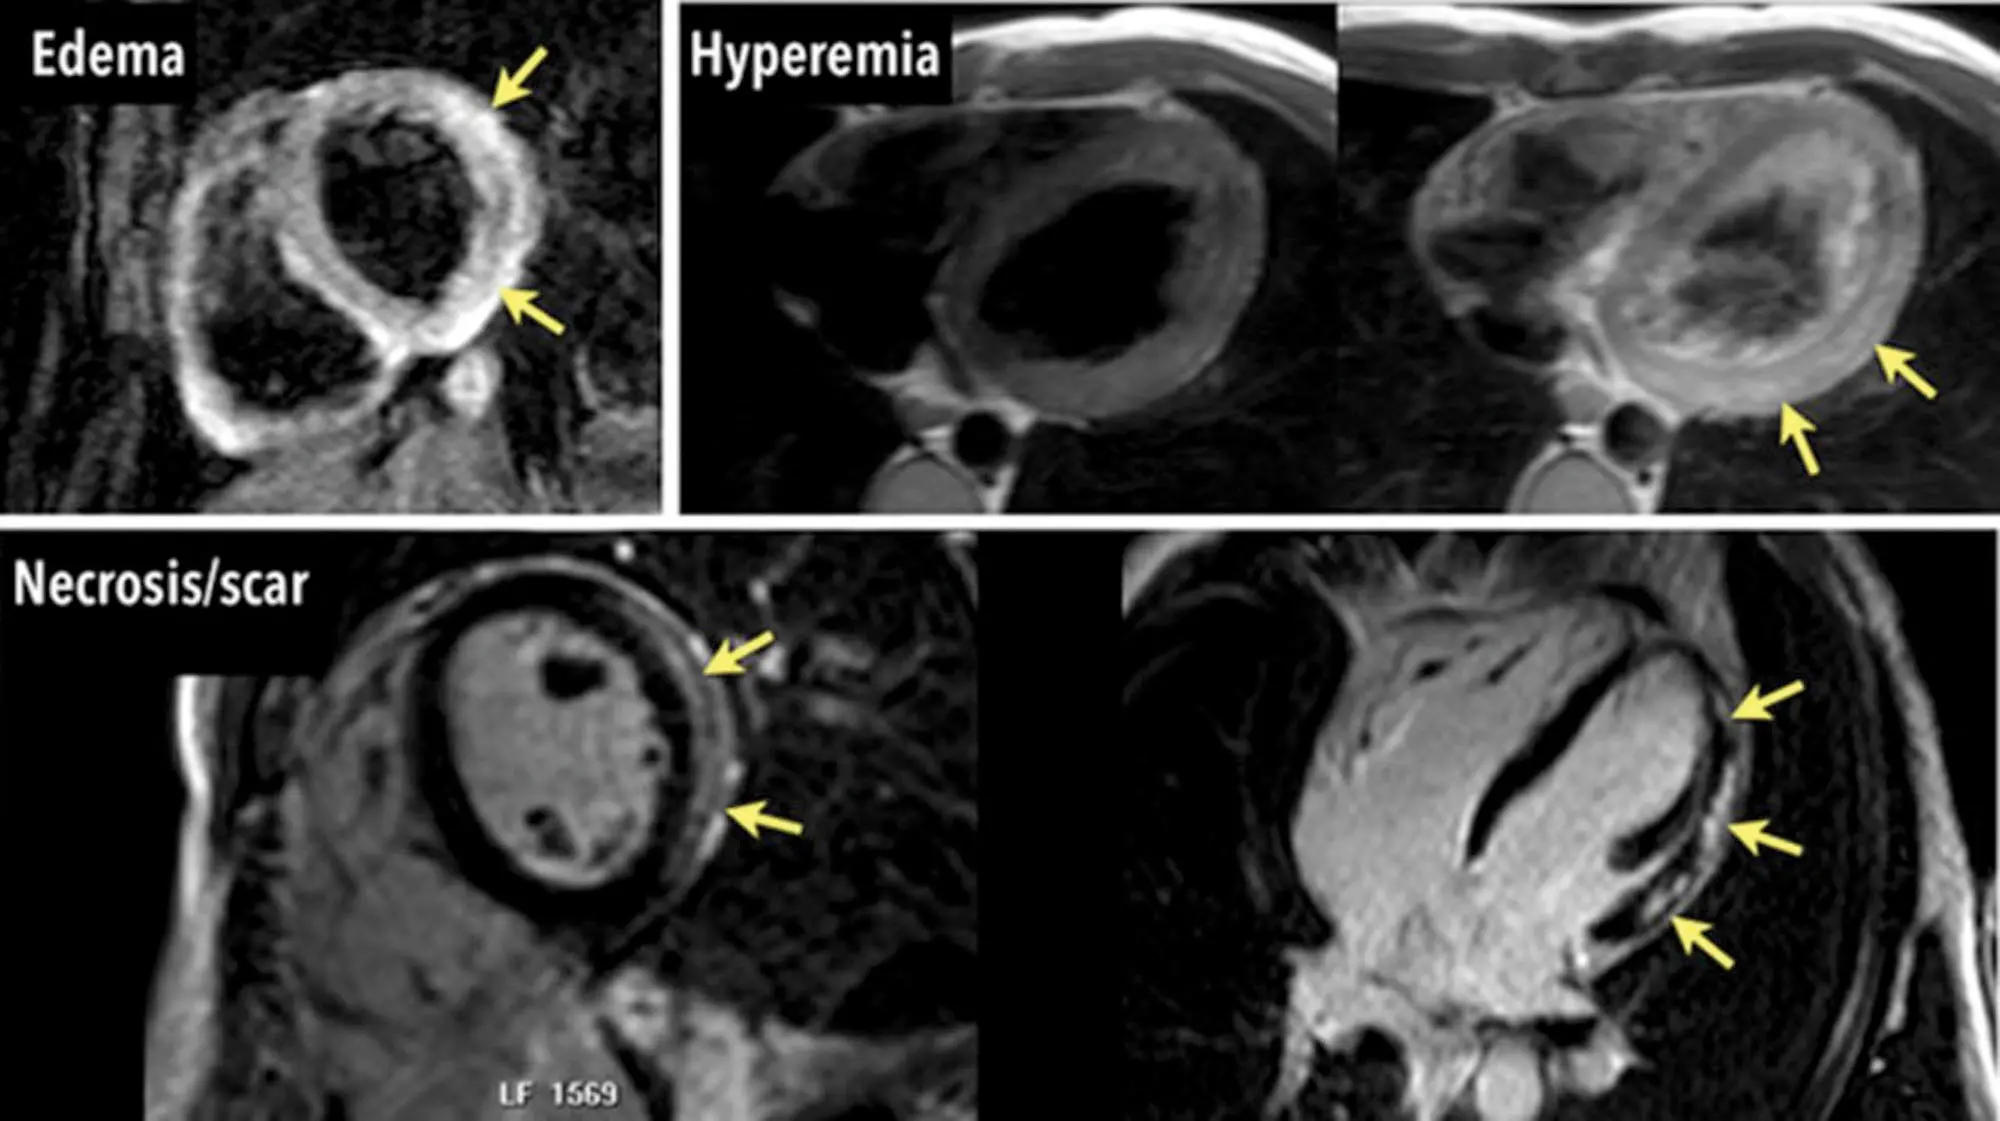

Figure caption: Cardiovascular magnetic resonance criteria for myocarditis (Lake Louise Criteria) in the same patients: regional myocardial edema (top left), hyperemia in images acquired early after contrast injection (top right), and inflammatory necrosis in images acquired late (>10 minutes) after contrast injection (bottom). All 3 criteria are positive. (Source)